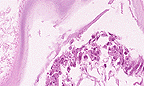

Classic lesion of clostridial enteritis, with numerous robust gram-positive bacilli lining necrotic villar remnants. (40X, Brown-Hopp's, 101K)

Contributor's Diagnosis and Comments: Marked to severe, diffuse, subacute, necrotizing enteritis with emphysema and intralesional bacilli.

This lesion is most consistent with necrotizing enteritis due to clostridial infection. Cultures were not done by the referring veterinarian but the morphology of the bacilli is consistent with Clostridium sp. Some clostridial species induce production of gas within tissues as they become established (gas gangrene) which has been attributed to a composite effect of toxins secreted by the organism.

AFIP Diagnosis: Small intestine: Enteritis, necrotizing, peracute to acute, diffuse, severe, with edema, hemorrhage, emphysema, and myriad mucosal adherent bacilli, breed unspecified, equine, etiology consistent with Clostridium spp.

Conference Note: Clostridial enterotoxemia is usually caused by Clostridium perfringens, a gram-positive, anaerobic, commensal bacillus. Clostridium perfringens has been subdivided into 5 substrains, A through E, depending on the combination of the four major exotoxins (alpha, beta, epsilon and iota toxin) produced. Alpha toxin is a lecithinase which degrades cell membranes. Beta toxin appears to paralyze the gut. Epsilon toxin is a proenzyme that is activated by enzymatic digestion by trypsin. Iota toxin is also a proenzyme that increases capillary permeability. Additionally, strains A, C, and D produce an enterotoxin. The enterotoxin is released only when the bacillus is lysed (thus, it is not an exotoxin) and is associated with the induction of diarrhea.

The majority of veterinary cases of clostridial enteritis in North America are caused by Clostridium perfringens Type C. The toxins produced by C. perfringens type C (alpha and beta toxin) produce a lesion in the intestine that is similar in appearance to autolysis. The villar mucosa is denuded of epithelium, often leaving only shrunken pegs of the lamina propria in place of the villi. The submucosa is expanded by edema and hemorrhage, and may contain neutrophils. There is often emphysema of the intestinal wall due to bacterial gas production.

Clostridium difficile is another cause of acute necrotizing enteritis in neonatal foals. C. difficile produces two toxins, A and B. Toxin A is an enterotoxin and toxin B is a cytotoxin that may act synergistically with Toxin A. The histologic lesion of C. difficile is similar to that of C. perfringens; culture and/or toxin identification is required to differentiate them.